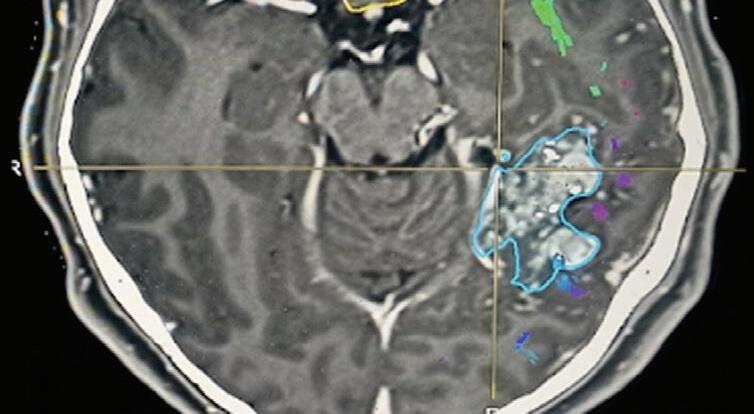

Fig. 1-14. RNM encéfalo, T2 axial (a) e coronal (b), demonstrando MAV grau 2 no lobo parietal esquerdo.

Arteriografia cerebral (c) AP e (d) em perfil, demonstrando a irrigação pelos ramos da artéria cerebral média (ACM) e anterior (ACA), com drenagem pela veia de Labbé, no seio transverso sigmoide.